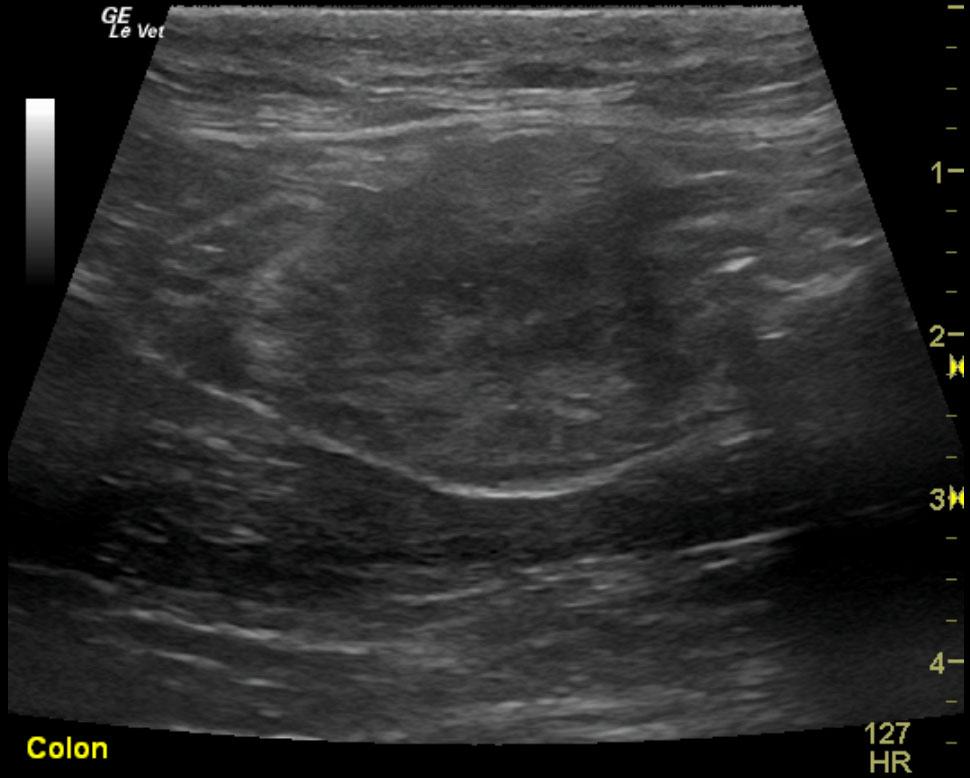

The patient is a feline DSH, MN, 8 year old. Concern for abdominal tumor due to decrease in appetite. Blood work is wnl. Urine specific gravity 1.045.